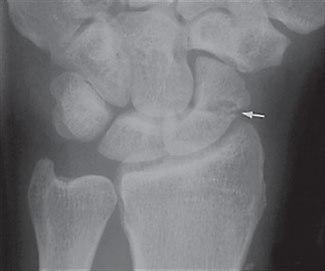

Etter skaden oppstår det umiddelbart smerter. Ofte ses ingen hevelse, men blødning i vevet kan føre til blålig misfarging på skadestedet etter noen dager. Legen får mistanke om tilstanden basert på skademekanismen, smertebildet og funn ved undersøkelsen. Typisk vil det fremkalle smerter hvis man klemmer i "snusdåsen" ved roten av tommelen - skafoidbeinet ligger like under huden her. Røntgen kan noen ganger bekrefte at det foreligger brudd (se røntgenbilde).

Imidlertid er bruddet ofte usynlig på røntgenbilder ved første undersøkelse. Hvis mistanken om brudd er sterk, men røntgenbildene er normale, henvises det vanligvis til CT eller MR for rask avklaring.